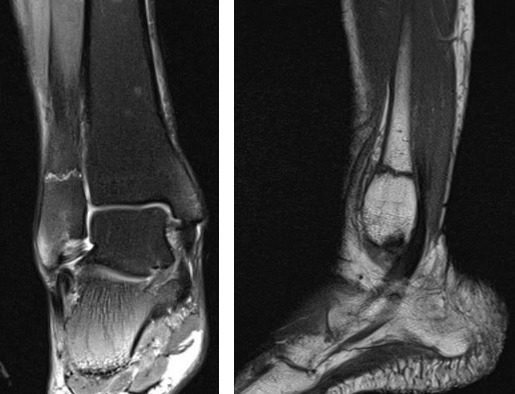

На Т2-ВИ в сагиттальной и корональной плоскостях определяется стресс-перелом дистальных отделов малоберцовой кости.

На Т2-fs-ВИ в сагиттальной плоскости определяется разрыва пяточного сухожилия.